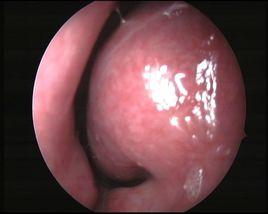

3. 鼻贅期:病期長久者由於患部皮脂腺和結締組織增生肥厚、血管擴張,致使鼻尖部肥大形成大小不等的結節狀隆起,稱為鼻贅。其表面凹凸不平皮脂腺口明顯擴大,擠壓時有白色粘稠的皮脂分泌物溢出,毛細血管顯著擴張。